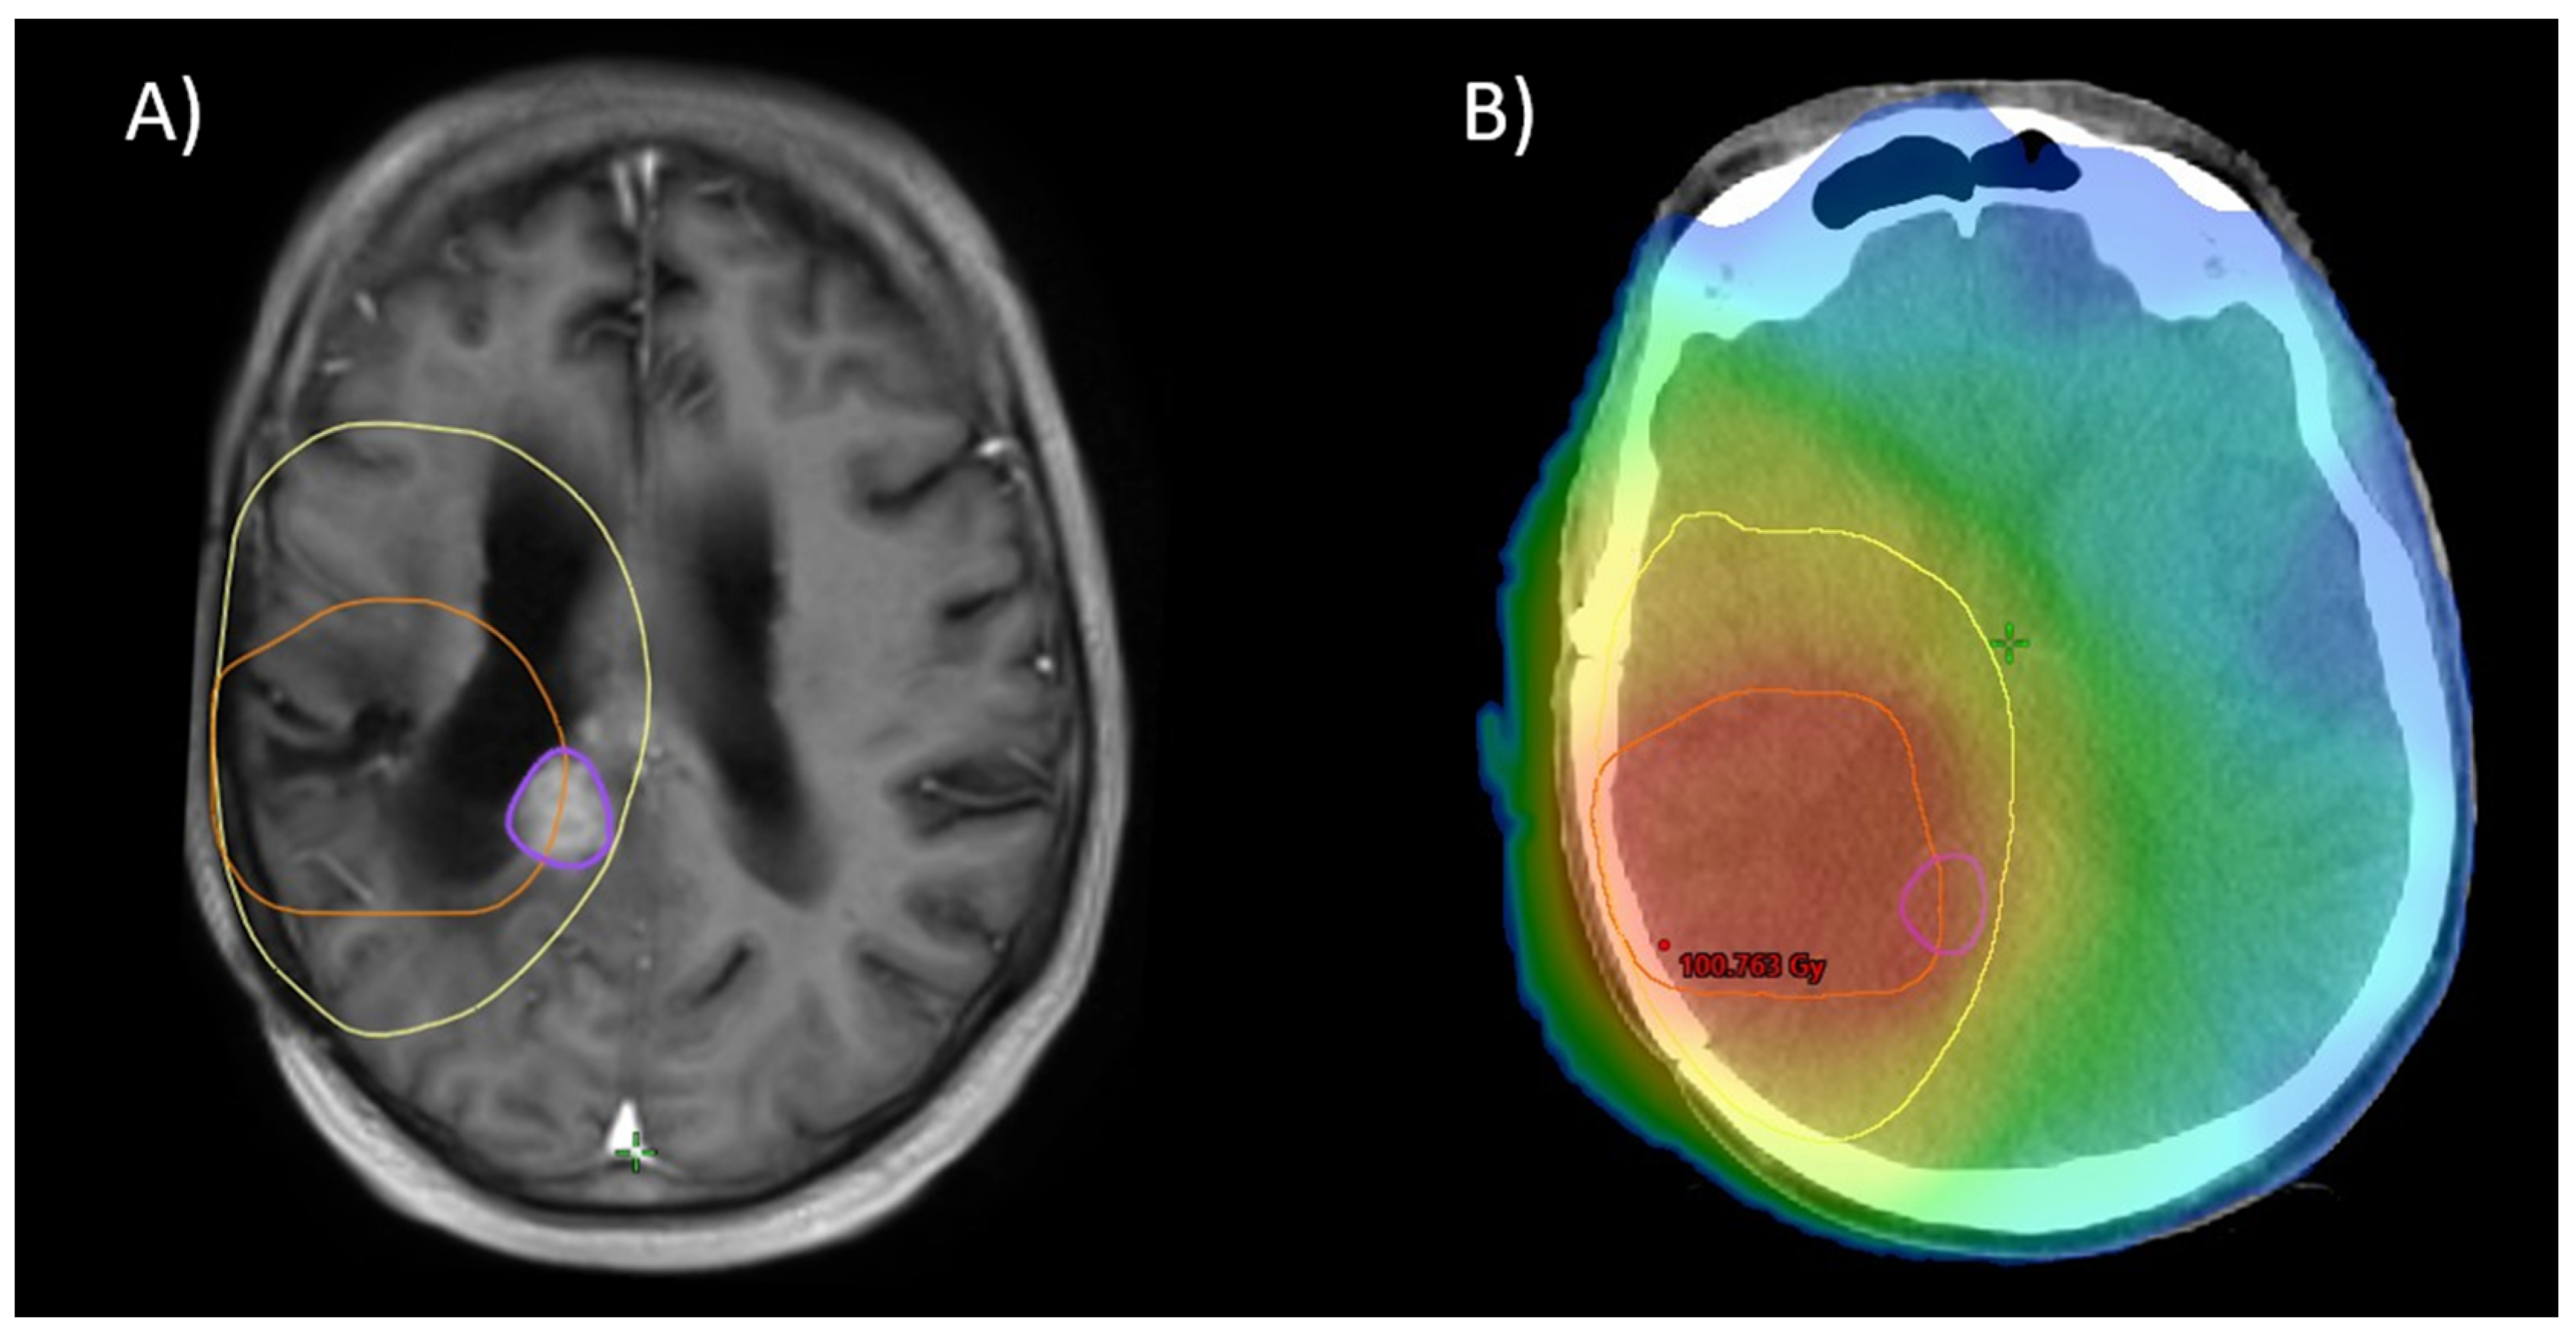

For 57 patients, the MRIs of further recurrence were all available in digital form. The patterns of relapse in these patients are described in Table 4, and a visual example is given in Figure 6. This analysis reveals no difference between the subgroups with in-field and marginal recurrence as the majority of cases (28 in-field recurrences, 26 marginal, 3 out-field). However, analysis of the initial patterns of relapse (leading to re-RT) reveals a tendency towards more out-of-field recurrence for patients treated with CeTeG (30% out-field vs. 14% for patients treated with TMZ, p = 0.11).

Figure 6.

As depicted in Figure 1, 12 months after re-RT: (A) Further progression (purple) adjacent to the initial treatment site. Notice the site of progression was covered by the initial PTV (yellow) and partially covered by the re-RT PTV (orange). (B) shows a color wash dose distribution of a plan sum of initial RT and re-RT.